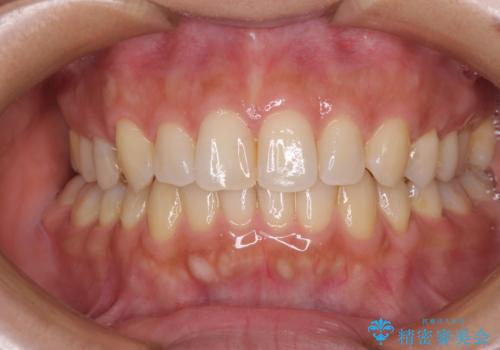

- 治療期間

- 3年8ヶ月

通院途中に、仕事の都合で東京に来る機会が激減してしまったため、なかなか治療が進まず、当初終了予定であった時期が2年近くずれ込んでしまいました。

今後もむし歯治療が必要となるため、日程を調整して沖縄から通院されるとのことでした。